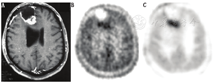

一经建立和验证,动力学模型可用于观察在任何单一时间点获得的静态PET图像的组成。也就是说,动力学分析可预测不同示踪剂药理学状态对总图像信号的影响。图5以18F-FDG为例,展示了对18F-FDG动力学的理解如何帮助诠释SUV。根据乳腺癌中的动力学常数范围[14]使用二室动力学模型生成曲线,图5描述了在肿瘤组织中检测到的18F标记的游离(18F-FDG)和捕获(18F-FDG-6-P)成分的影响。对于SUV较低的肿瘤,即使在注射后晚期,游离18F-FDG和捕获18F-FDG摄取也几乎相等。因此,适度摄取(SUV<3~4)的肿瘤的SUV反映出几乎相等的、混合的运输和组织分布(可逆组织18F-FDG)、葡萄糖代谢(18F-FDG-6-P)状态。然而,对于SUV高的肿瘤,注射后60 min,大多数标记物以18F-FDG-6-P的形式出现,60 min SUV提供了肿瘤糖代谢的合理指示。这一观点有几个重要意义:首先,对于基线摄取较低的肿瘤,应仔细解释治疗后摄取的变化,因为其可能反映了作为治疗的不良反应的示踪剂释放或组织分布的变化,而不是葡萄糖代谢所示的肿瘤生存能力的变化。同样,18F-FDG摄取量低也可能影响治疗后肿瘤摄取量测量的准确性和解释,治疗后肿瘤的摄取量通常携带预后信息,通过动力学参数(如Ki)可比静态显像指标(如SUV)更准确地测量这些信息[14]。